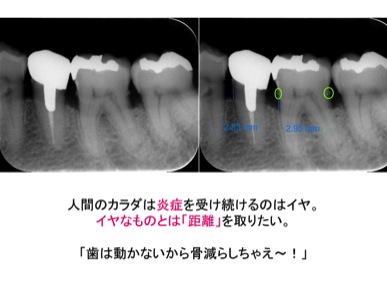

ちょっと悲しい話をしますね。実は、歯周病というのは細菌の感染から逃げるための人間の炎症反応、防御反応なんです。

こういうことです↓

となって、歯を支える土台の骨を溶かして、細菌でカラダに悪影響の出ないようにいい感じの距離を取るのです。鏡でお口の中をよくみて下さい。下アゴの歯の舌側になにか白いのがついていませんか?

歯石はカルシウムの塊。サンゴ礁みたいに穴がたくさん空いていて、そこがいわば細菌の住まいになって周りに毒素を出しているんです。

そして、歯周病菌は空気のない使いところが住みやすいので、どんどん深いところへ、下へ下へと侵食していきます。

更に、深くまで進み、歯の支えの骨が全部なくなって、歯槽膿漏へと悪化。こうなってしまって噛んで痛い、と言われると悲しいですが抜歯するしかありません。